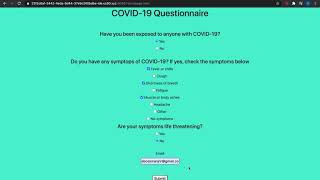

Covid-19 Safety Check In by Aric Duncan Mazick

A web app that employees will fill out prior to each shift to ensure they're not at risk of transmitting Covid-19.